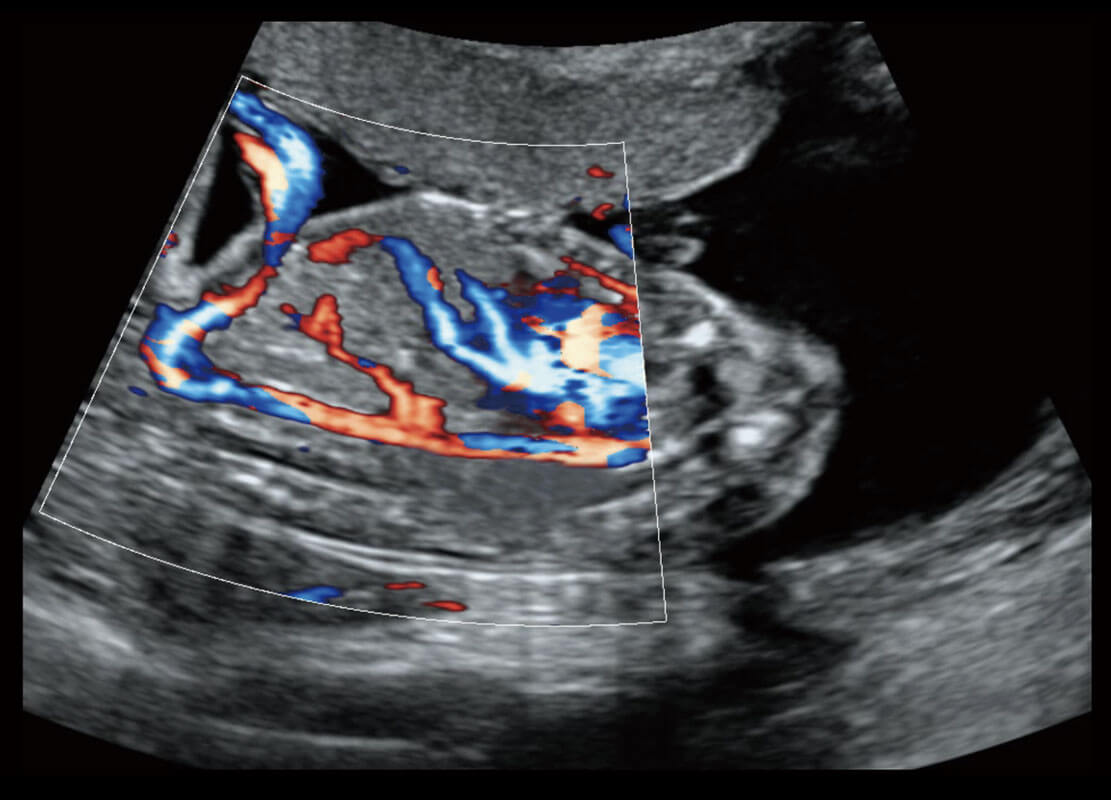

P60搭载一系列胎儿心脏成像技术,实现精细的胎儿心脏评估。

四腔切面

四腔心血流

胎心容积成像